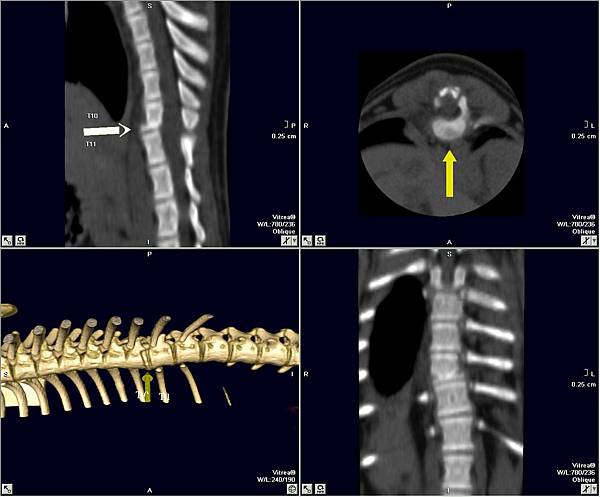

肉粽是一位三個月大的柴犬

被壓傷導致脊椎骨折(第十胸椎)

脊椎骨折是非常緊急的手術

趕緊安排手術